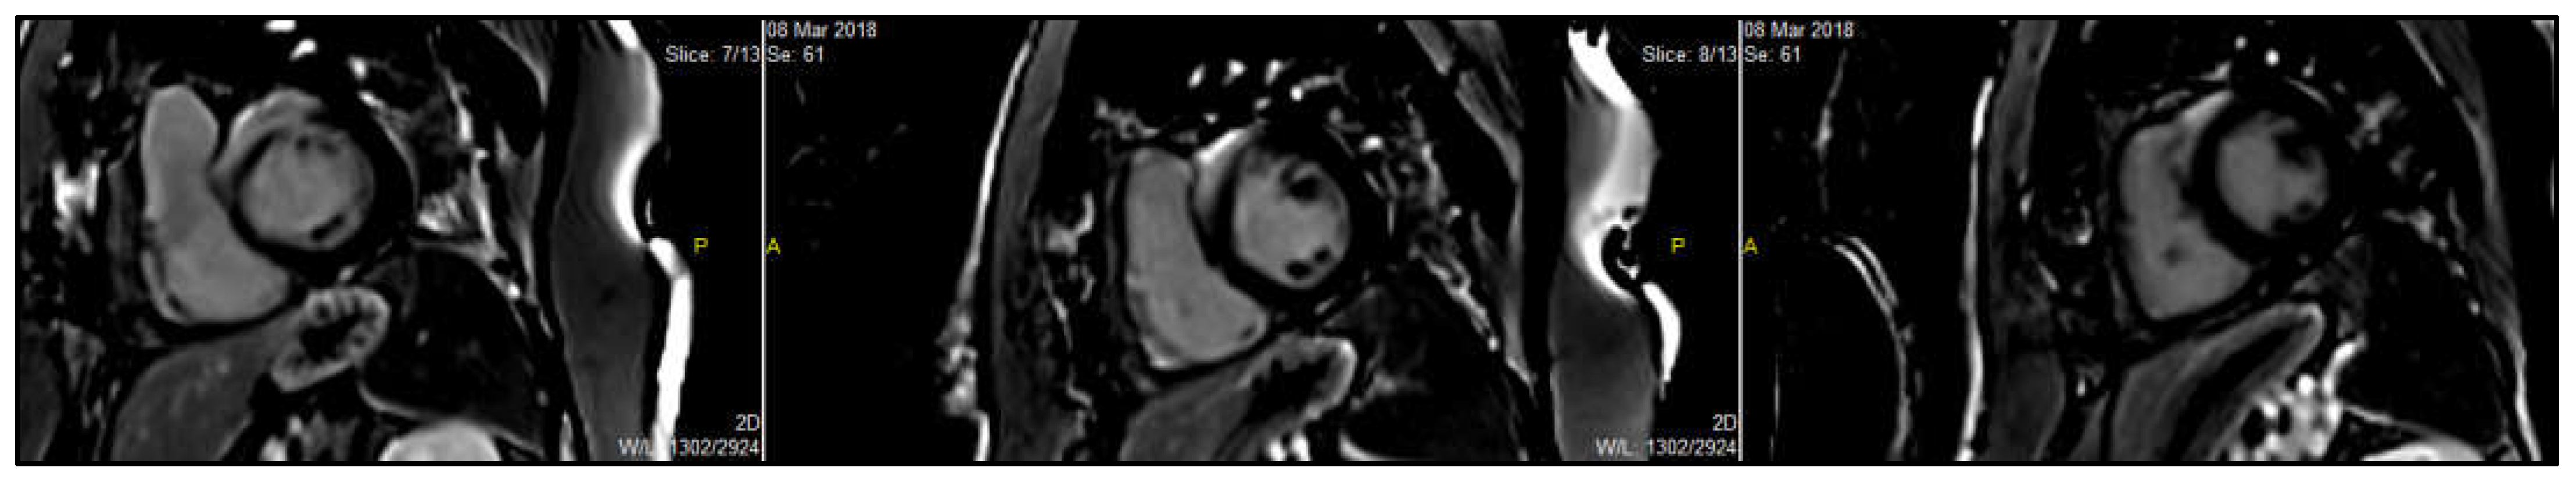

Figure 6. Characteristic cardiac MRI findings in different HF etiologies. (a): Four chamber delayed enhancement CMR in a patient with myocarditis. Late gadolinium enhancement (LGE) is seen in the mid-myocardial to subepicardial layers of the anterolateral wall, a typical non-ischemic pattern of injury. These findings are consistent with inflammatory myocardial involvement, commonly seen in viral or immune-mediated myocarditis. (b): Cardiac magnetic resonance (CMR) image demonstrating ischemic cardiomyopathy. The image reveals marked apical thinning with transmural late gadolinium enhancement (LGE) in the left anterior descending (LAD) artery territory, consistent with chronic infarction and scar formation. These findings are typical of prior anterior myocardial infarction with associated adverse remodeling. (c): 4-ch delayed enhancement CMR in apical HCM showing mid-septal LV hypertrophy and apical scar. (d): Short-axis LGE image revealing inferolateral mid-myocardial to epicardial lateral wall hyper-enhancement and concentric LV hypertrophy in Fabry’s disease. (e): Cardiac magnetic resonance imaging (CMR) in the 4-chamber view with late gadolinium enhancement (LGE) in a patient with cardiac amyloidosis. The image demonstrates diffuse, global subendocardial, and transmural late gadolinium enhancement, a hallmark feature of cardiac amyloid infiltration. Note the difficulty in nulling the myocardial signal, another characteristic finding in cardiac amyloidosis. (f): Cardiac magnetic resonance (CMR) image in a patient with endomyocardial fibrosis (EMF). The four-chamber late gadolinium enhancement (LGE) image demonstrates apical scarring with superimposed thrombus in the left ventricle, characteristic of EMF, and reflects chronic fibrotic remodeling leading to restrictive physiology. (g): T2* relaxation curve showing exponential signal decay over time, characteristic of myocardial iron overload. The yellow line represents the T2 relaxation process, which describes the decay of transverse magnetization due to interactions between nearby spins. The black line shows the T1 relaxation process, which depicts the recovery of longitudinal magnetization as spins realign with the external magnetic field. These curves are fundamental for differentiating tissue types in MRI based on their distinct relaxation times. The rapid drop in signal intensity reflects shortened T2* values due to increased magnetic susceptibility from iron deposition. Quantitative T2* analysis is essential for assessing the severity of cardiac siderosis, particularly in conditions such as thalassemia major or hemochromatosis. (h): LV cine image displaying prominent trabeculations and deep intertrabecular recesses, predominantly in the apical and lateral segments characteristic of left ventricular non-compaction (LVNC). (i): Short-axis cardiac magnetic resonance (CMR) image of the mid-left ventricle used for T2* mapping. The green line represents the outer boundary of the myocardial wall, while the red line indicates the inner endocardial lining. The region of interest (ROI) (in yellow) is typically placed in the interventricular septum to quantify myocardial T2* relaxation times. This technique is essential for detecting and monitoring myocardial iron overload, with lower T2* values indicating increased iron deposition.

Figure 7. CMR image of a patient with cardiac sarcoidosis. Short-axis CMR image showing mid left ventricular patchy late gadolinium enhancement (LGE) in the basal septum and anterior wall with RV involvement, suggestive of cardiac sarcoidosis. (In the image, P = posterior; A = anterior).